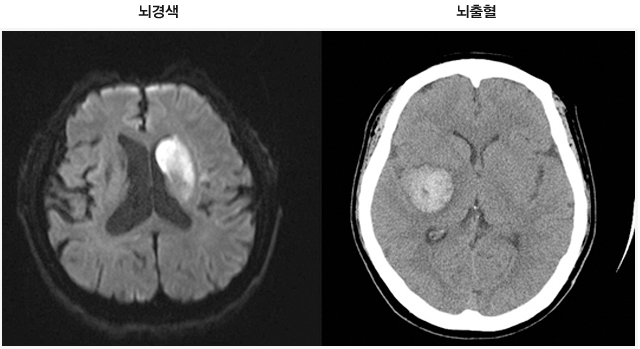

뇌졸중이란 뇌혈관의 이상에 의해 뇌혈관이 막히거나 터져 뇌의 국소 또는 전반적인 뇌 기능 장애를 일으키는 것을 말한다. 뇌경색은 크게 두 가지로 나뉜다. 뇌혈관이 막혀 뇌에 허혈성 변화로 인해 나타나는 뇌경색과 뇌혈관의 출혈로 인해 뇌에 피가 고이는 뇌출혈이다. 우리나라의 뇌졸중의 약 15%는 출혈성 뇌졸중이고, 나머지는 허혈성 뇌졸중으로 뇌졸중의 다수를 차지한다.

1. CT (컴퓨터 단층 촬영 )

CT 검사는 뇌경색과 뇌출혈을 구분하고 특히 뇌출혈을 빠르게 감별 진단할 수 있다. 단, 뇌경색의 경우 일정 시간이 지나야 병변이 보이기 때문에 초기에 CT 검사로 진단하기 어렵고, 뇌출혈은 출혈 발생 후 CT에 바로 나타나기 때문에 뇌출혈 진단에 유용하다.

2. MRI (자기 공명 영상 )

뇌경색 부위와 뇌혈관의 협착 및 폐쇄 여부를 확인할 수 있다. CT에 비해 뇌출혈 진단 능력은 비슷하나 초기 뇌경색 및 범위가 작은 뇌경색 등도 진단이 가능하다. 단, 검사 시 금속성 물질을 부착한 (인공 심박기 등) 경우 검사의 어려움이 있다.